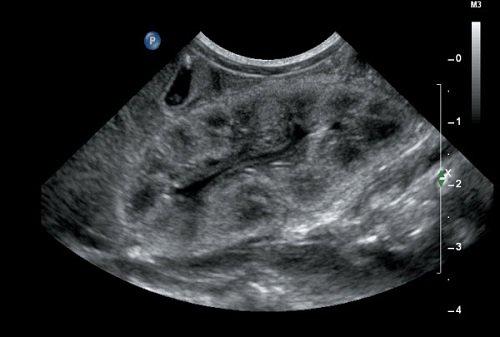

Bệnh về thận là một trong những bệnh nguy hiểm đến sức khỏe và khó kiểm soát. Trong khi đây lại là bộ phận quan trọng, giữ nhiều nhiệm vụ trong cơ thể con người. Lúc này, siêu âm thận là phương pháp hữu hiệu trong phát hiện, chẩn đoán các bệnh về thận. Hôm nay, hãy cùng MEDLATEC tìm hiểu những th...

Siêu âm thận được chỉ định đối với trường hợp nào?

Hiện nay, số lượng người mắc các bệnh liên quan đến thận, đường tiết niệu ngày càng gia tăng. Để phát hiện ra các bệnh lý liên quan đến thận, siêu âm là một phương pháp hữu hiệu. Tại sao cần phải siêu âm thận, nó phát hiện được những bệnh lý nào, bài viết chính là câu trả lời cho bạn.